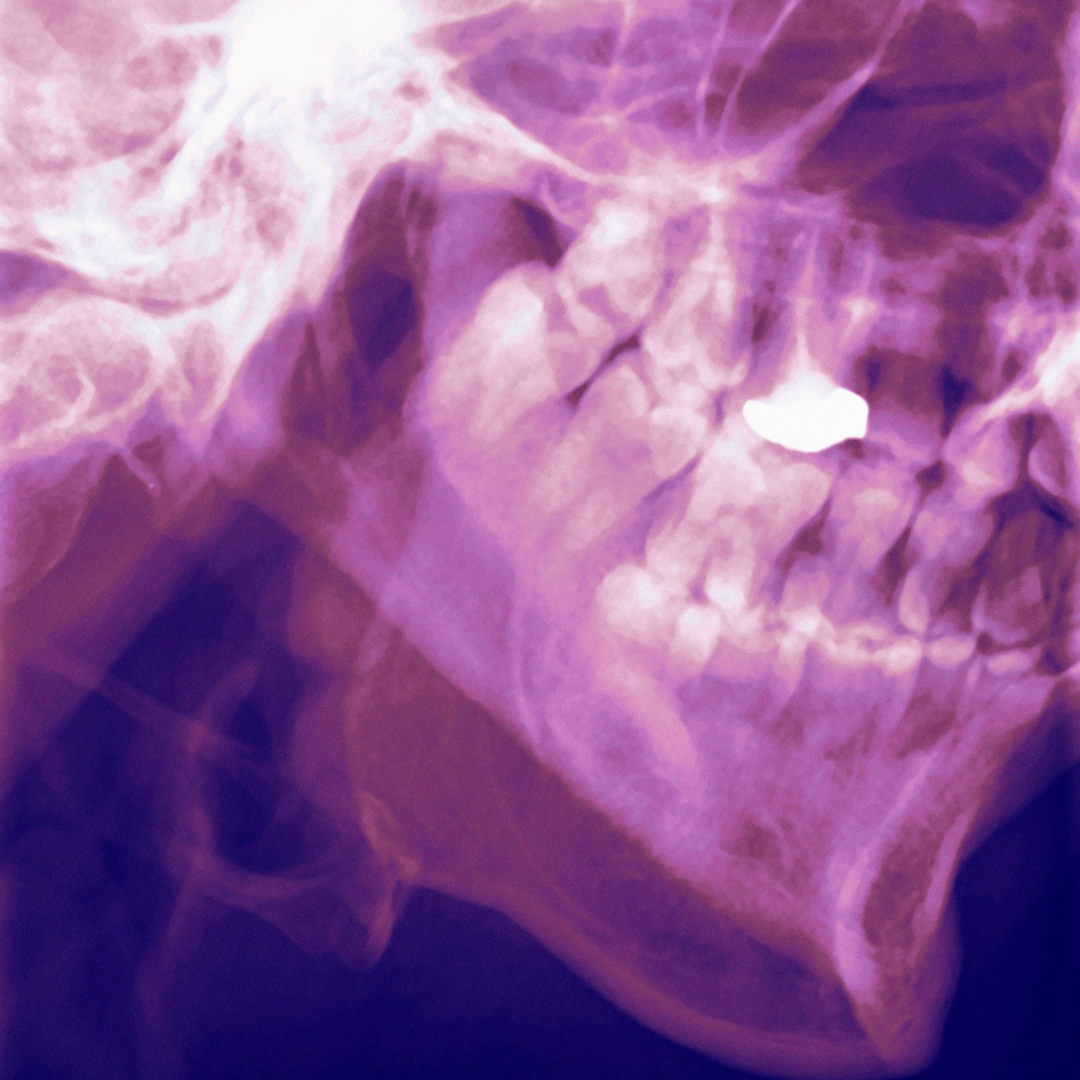

- Comprehensive Evaluation: Dr. Scott Bonin will perform a thorough examination, including a review of your medical history, a physical exam of your jaw, and imaging tests such as X-rays or MRI if needed.